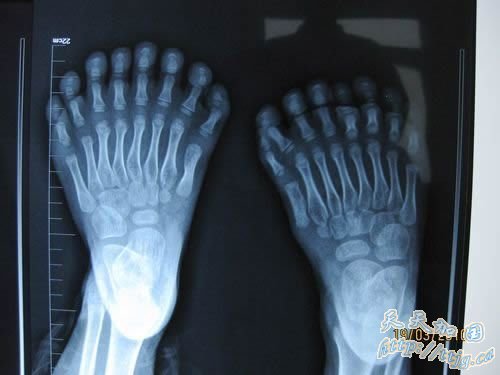

鹏鹏的手指和脚趾长得“很特别”,小鹏鹏的手指有15根,脚趾有16根,加起来就是31根,令人奇怪的是,他的每只脚上都长有8根脚趾,且长得还很匀称,散开看酷似“莲花掌”,而手指长得就更奇了,有散开长的,还有并着长在一起的,一只手长有7根,另一只是8根。

资料显示,印度22岁的小伙子哈拉姆,手指长了12根,脚趾有16根(有的是并着长的),但后来一位13岁的印度小孩子“刷新”了这一记录:12根手指、13根脚趾,全是分开长的。然而不管是并着算,还是分开算,鹏鹏确实是目前世界上手指和脚趾长得最多的人。

“手术需要4至5小时,最难的是两手,其中,要再造一个‘虎口’,左手三个并指还要切掉中间的一根,创面还要修复好……相对来说,脚趾的手术简单、容易一些,要将每只脚最外侧多余的三个脚趾切掉,然后修复好脚掌,让他和正常人一样!”